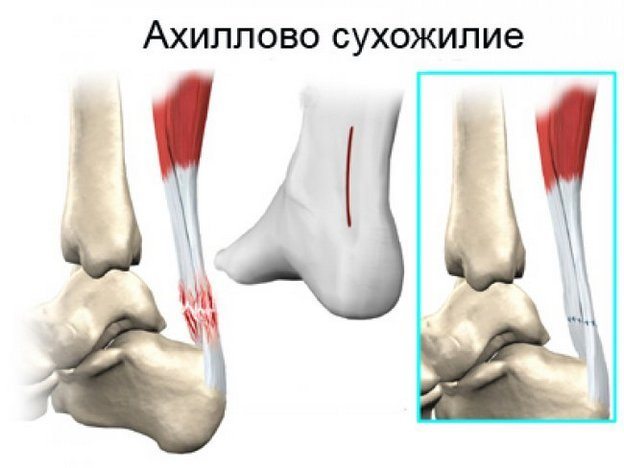

Ахиллит

Ахиллово сухожилие воспаляется из-за чрезмерных постоянных нагрузок и ношения узкой обуви на высоких каблуках. Ведущий симптом ахиллита — боль в пяточной области, усиливающаяся при движении. На воспаление сухожилия также указывает отечность, припухлость кожи.

Если человек не обращается за медицинской помощью, то при резком снижении иммунитета развивается гнойный процесс. В этом случае становится невозможным передвижение даже по комнате. При остром течении воспалительного процесса возможен разрыв волокон сухожилия.